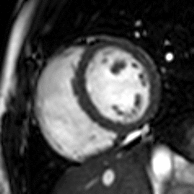

Atrial septal defect with dilation of the right ventricle by CMR

Partial Anomalous Pulmonary Venous Drainage by CMR

Enlarged right ventricle with poor function in a patient with repaired tetralogy of Fallot by CMR